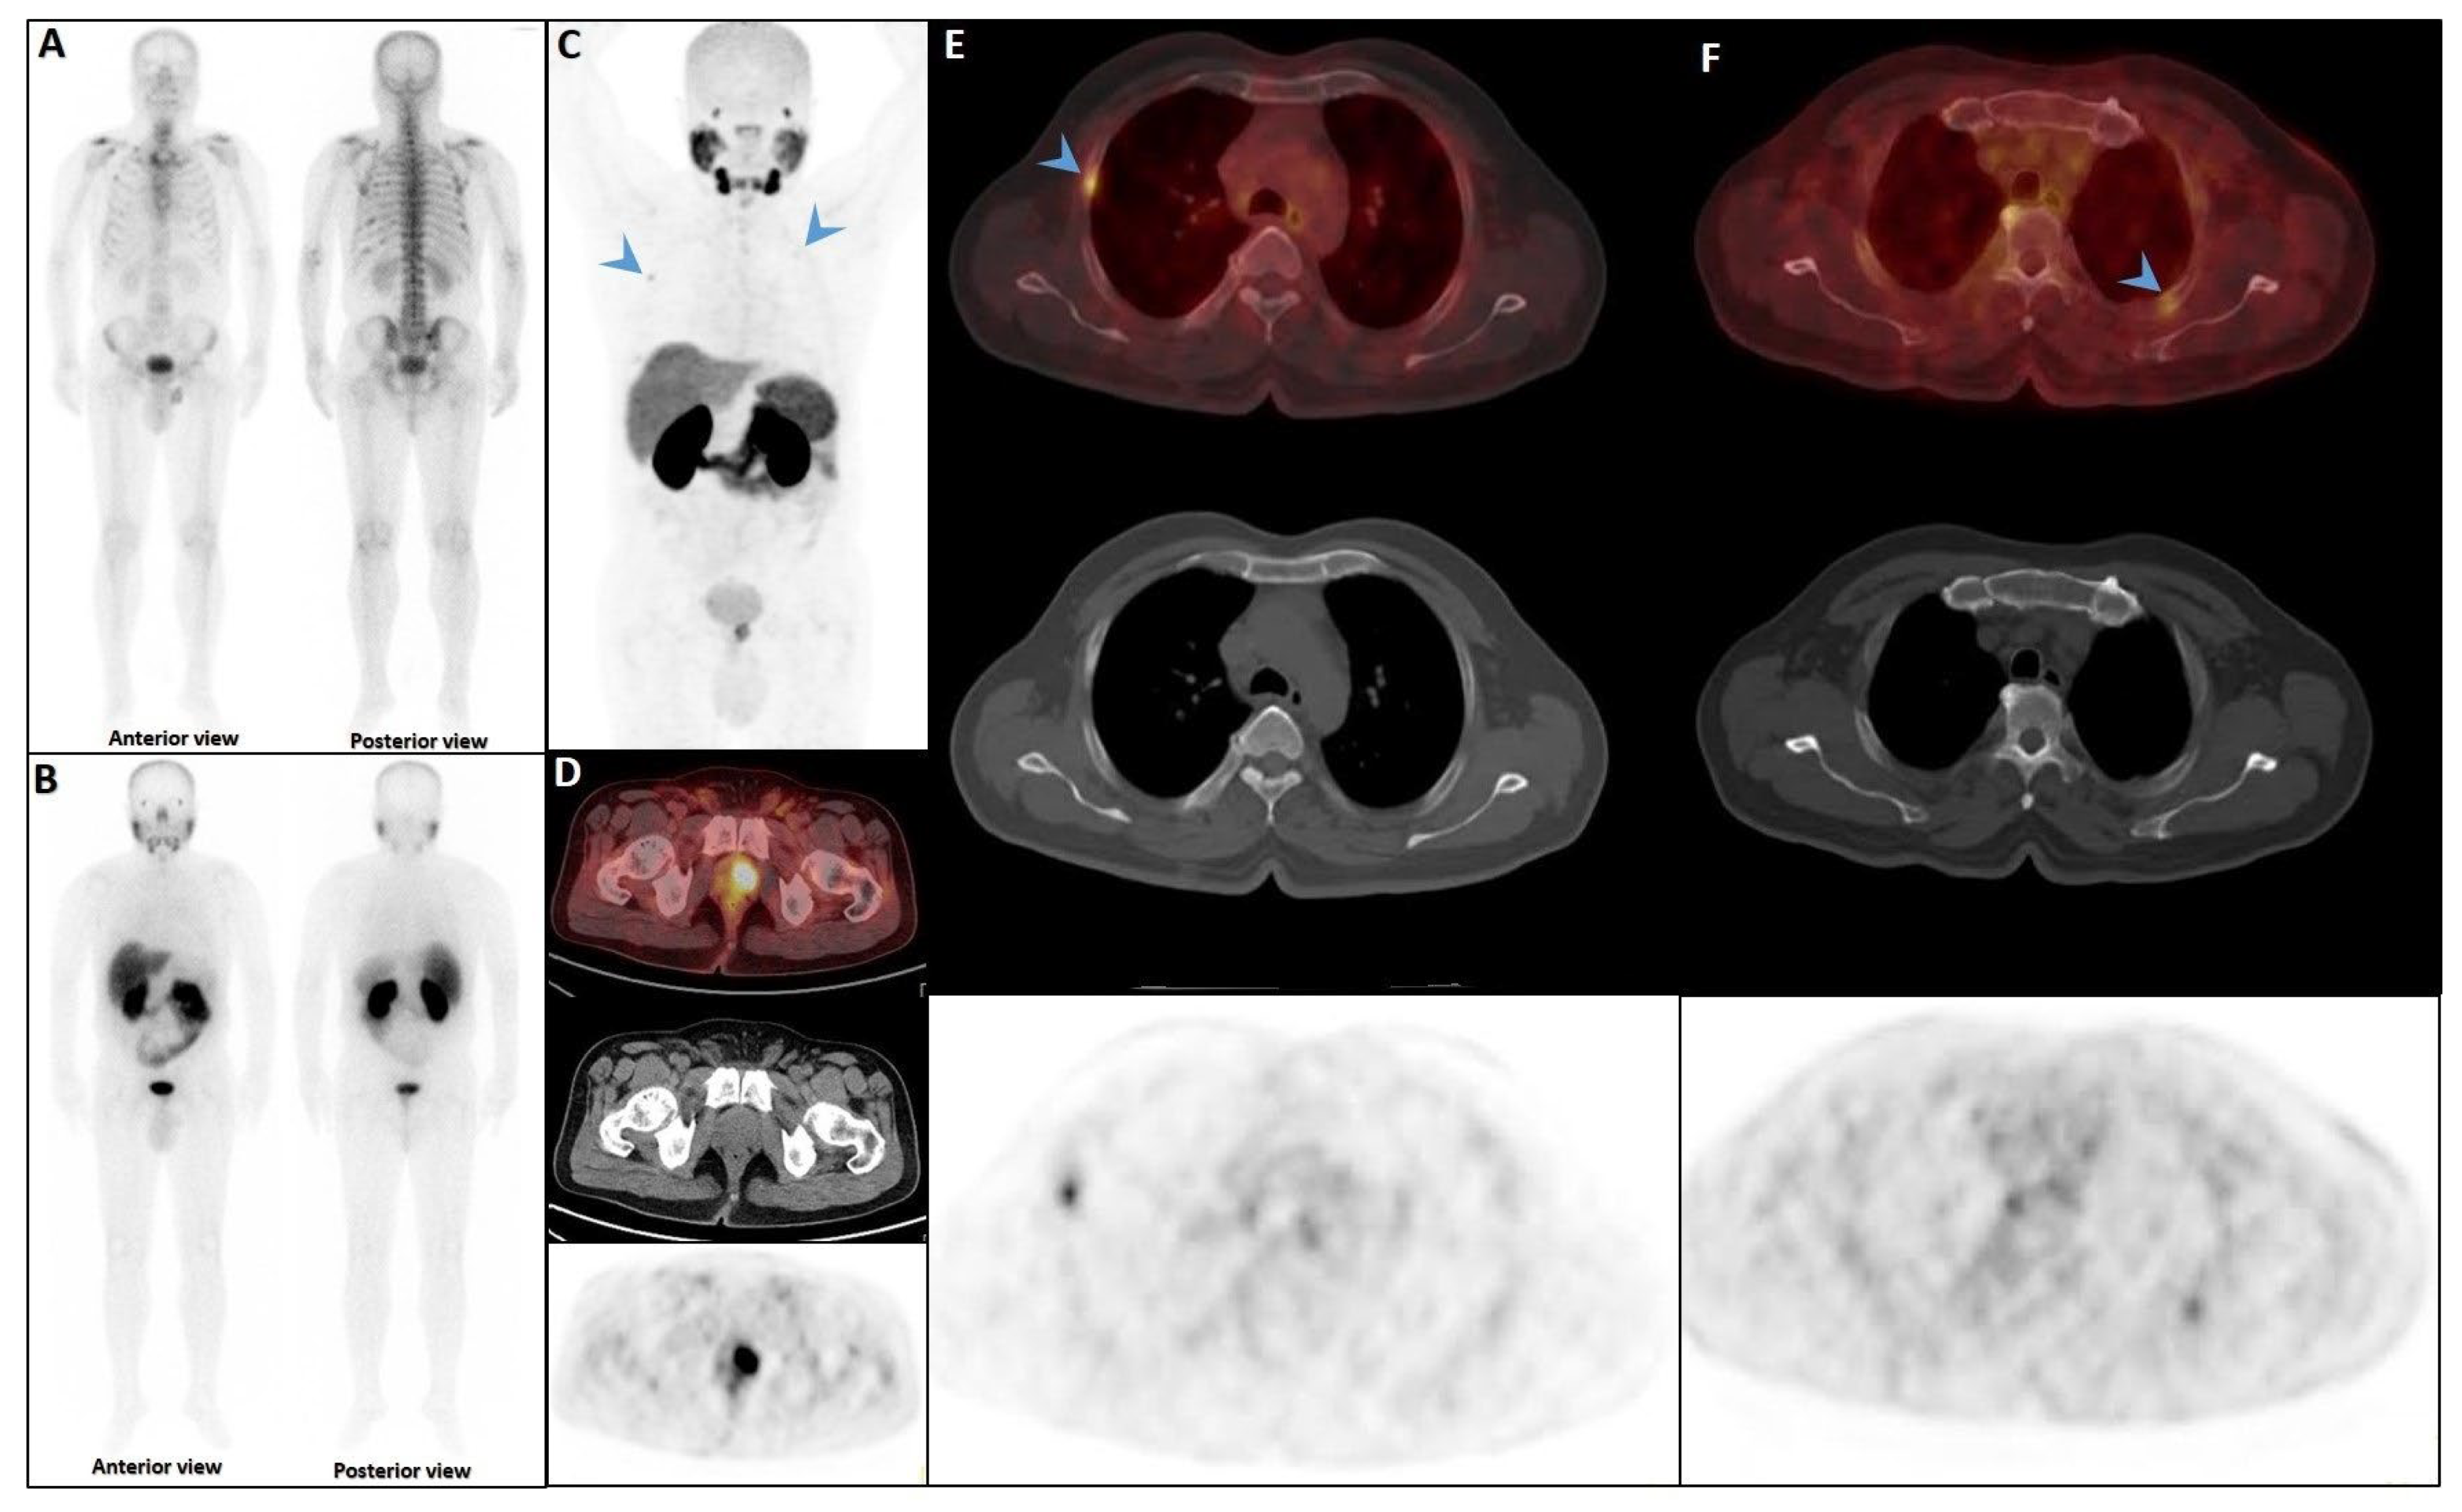

| First Author | Rate of Rib Lesions | Metastatic Rib Lesions | Isolated Rib (%) | Multiple Rib/Multifocal Uptake (%) | Rib SUV Range |

|---|---|---|---|---|---|

| Studies with 68Ga-PSMA-11 | |||||

| Stoffels—2025 [7] | 100% patients (inclusion criteria) | 14.8% (8/54) Cat I and III | - | 18.5% (10/54 patients had multiple rib lesions) | Mean: 2.90 (benign) and 4.8 (malignant) |

| Zacho—2020 [91] | 6.25% (7/112) patients | No metastasis Cat II | 100% | 0% | - |

| Chen—2020 [40] | 2.3% (111/4792) (62 of them had staging scans) | 1.6% (1/62) Cat I, III, IV | 100% (inclusion criteria) | - | Mean SUVmax: 2.21(malignant) 3.02(benign) |

| Sareni—2023 [132] | 11.2% (20/179) | - | 3.4% (6/179) | 14/20 (70%) had additional bone sites (Multi focal) | Median SUVmax: 13.8 (all lesions) |

| Chiu—2020 [92] | 33.9% (19/56) | 79% (15/19) Cat II | - | - | - |

| Mainta—2024 [99] | 30.6% | 33.3% Cat II | - | - | Mean SUVmax: 4.6 (all lesions) |

| Simsek—2020 [100] | 22.1% (25/113) | 25/26 (96%) Cat II | - | (ribs + other sites): ~23.9% | - |

| Dancheva—2024 [133] | 12.5% (5/40) | 0% Cat III/IV | - | (symmetrical/multiple in ribs) ~23% | 1.0–3.4 (bone lesions incl. ribs) |

| Shah—2025 [134] | 4.9% (72/1480) | 30.6% (22/72) Cat I/III/IV | Malignant: 40.9% (9/22); Benign: 51.6% (16/31) | (solitary focus; non-isolated: 59.1% with other mets) | Median range for lesions: Malignant: 4.31 (2.63–10.44); Benign: 2.18 (1.6–2.7) |

| Studies with 18F-PSMA-1007 | |||||

| Luo—2024 [135] | 37.3% (59/158) | 11.8% (7/59) Cat I and II | - | - | - |

| Arnfield—2021 [13] | 61.3% (122/199) | No metastasis Cat II | - | - | - |

| Benecke—2024 [136] | 50% (115/230) | 2% Cat IV | - | - | SUVmax range: 2.9–16.1(metastatic) |

| Grünig—2021 [12] | 57.5% | - | - | - | Mean SUVmax: 3.8 (all lesions) |

| Bauckneht—2024 [137] | 145/448(32.4%) | 28.3% (41/145) Cat II | - | - | - |

| Hoberück—2023 [138] | 58.7% (27/46) | - | - | - | - |

| Orevi—2022 [93] | 40% (35/14) | No metastasis Cat III | 11.8% solitary rib foci | Multifocal (including ribs and other sites): 29.4% | - |

| Seifert—2023 [139] | 38.2% (13/34) | No metastasis Cat II | - | - | |

| Fragkiadaki—2024 [140] | 19.2% (20/104) | 100% all metastatic Cat II | - | - | SUVmax range: 2.30–77.32 (all lesions) |

| Panagiotidis—2023 [141] | 14%(26/186) | - | - | - | - |

| Studies with 18F-DCFPyL | |||||

| Woo—2025 [17] | 100% (175/175) | 47/175 (26.9%) Cat II | 0.57% (1/175) for metastatic isolated rib lesions 54.9% (96/175) for single rib lesions with no other metastases | Multiple rib lesions only: 9.1% Multifocal (ribs + other sites): 24.0% (42/175) | Mean SUVmax and range: 1.8 (1.4, 2.6) (benign) 7.7 (2.7, 16.5) (malignant) |

| Ulaner—2022 [142] | 11.7% (7/60) | 57.1% (4/7) Cat I | 100% | - | - |

| Phelps—2022 [143] | 39/98(39.8%) | 23% (9/39) Cat I and II | - | - | SUVmax range: (2.4 to 15.2) |

| Yin—2019 [144] | 12/46(26.1%) | 25% (3/12) Cat IV | - | - | Median SUVmax and range: 1.15, (0.85–1.89) |